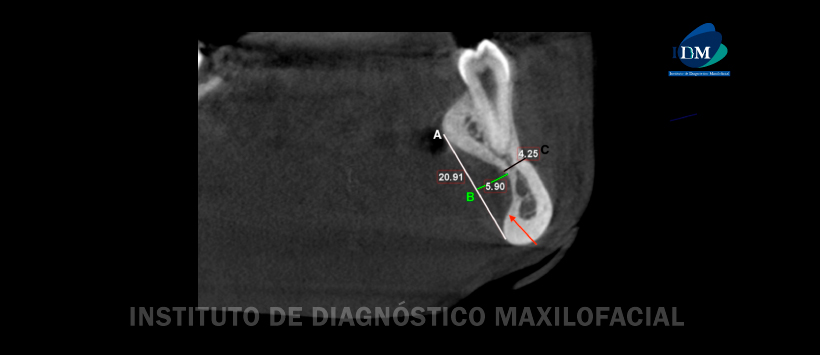

Para evaluar la profundidad y el ancho de estas depresiones, las imágenes CBCT se reconstruyeron en planos alineados con los ejes de los segundos premolares mandibulares derecho e izquierdo en la dimensión mesiodistal, la dimensión bucolingual y la dimensión coronoapical. Luego, se realizaron mediciones lineales que representan el ancho de las depresiones a lo largo de una línea dibujada tangente a las alturas de los contornos (cresta de curvaturas) de las superficies linguales de la mandíbula superior e inferior a la depresión bilateral. Se encontró que el ancho superoinferior de las depresiones era 2.1 cm en el lado derecho y 2.9 cm en el lado izquierdo. Las mediciones lineales que representan la profundidad bucolingual de las depresiones que se realizaron a lo largo de una línea trazada perpendicular a la línea de ancho mencionada anteriormente hasta el punto más profundo de la depresión; medía 0,59 cm en el lado izquierdo y 0,6 cm en el lado derecho. El grosor bucolingual de la mandíbula restante era de 0,42 cm en el lado izquierdo y de 0,45 cm en el lado derecho (Figuras 2-3).